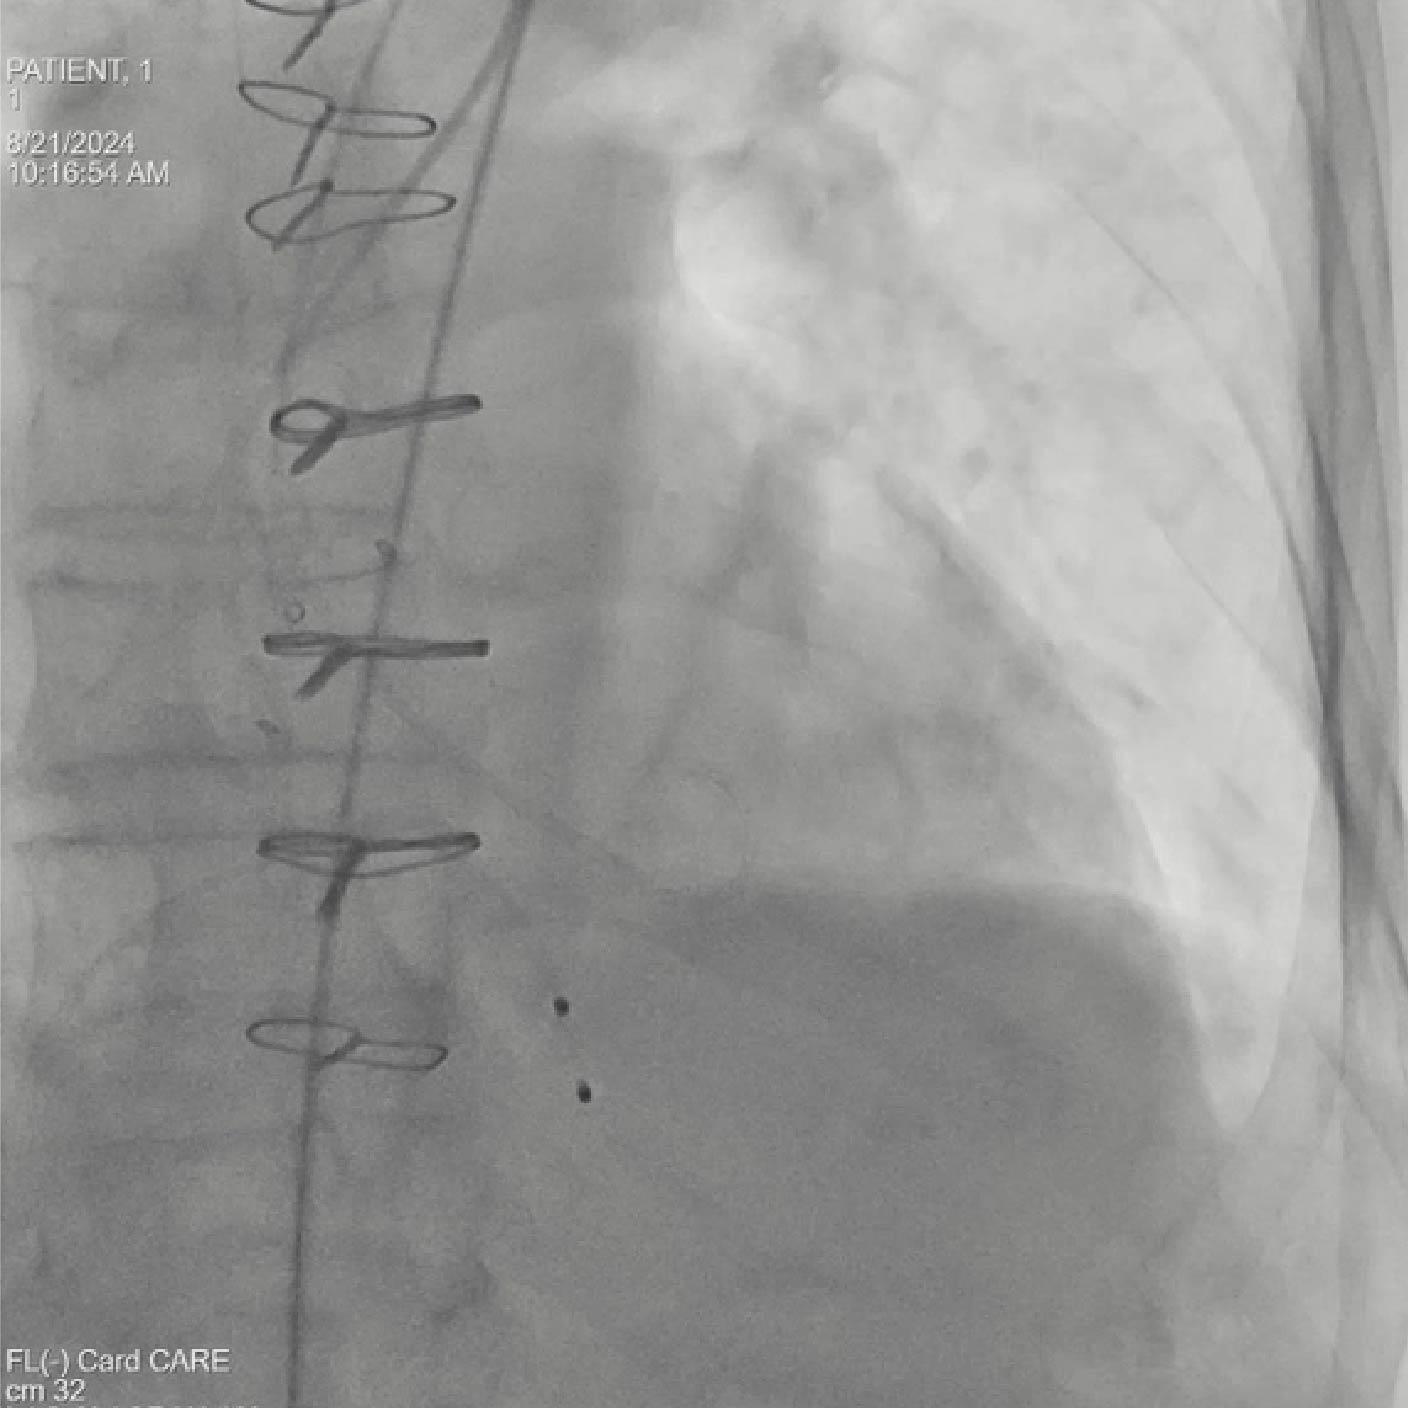

Posicionamiento y despliegue del dispositivo

Objetivo clínico: Soporte para la colocación de un dispositivo de protección cerebral como herramienta para mitigar el riesgo de accidente cerebrovascular embólico.

Soluciones y características seleccionadas: ARTIS pheno, Case Flows, Una combinación preestablecida de configuraciones (angulación, disposición de la pantalla, etc.), personalizada para la colocación del dispositivo SENTINEL™*, reduce las interacciones con el sistema. Con Case Flows, una única interacción del usuario reemplaza el ajuste de hasta 6 configuraciones del sistema³. syngo 2D/3D Fusion - Aplicación para superponer la anatomía de la arco aórtico basada en tomografía computarizada sobre fluoroscopia en vivo, para apoyar la navegación del dispositivo. Se ha demostrado que la guía por fusión reduce significativamente el tiempo de despliegue del dispositivo SENTINEL™* y el uso de contraste⁴.